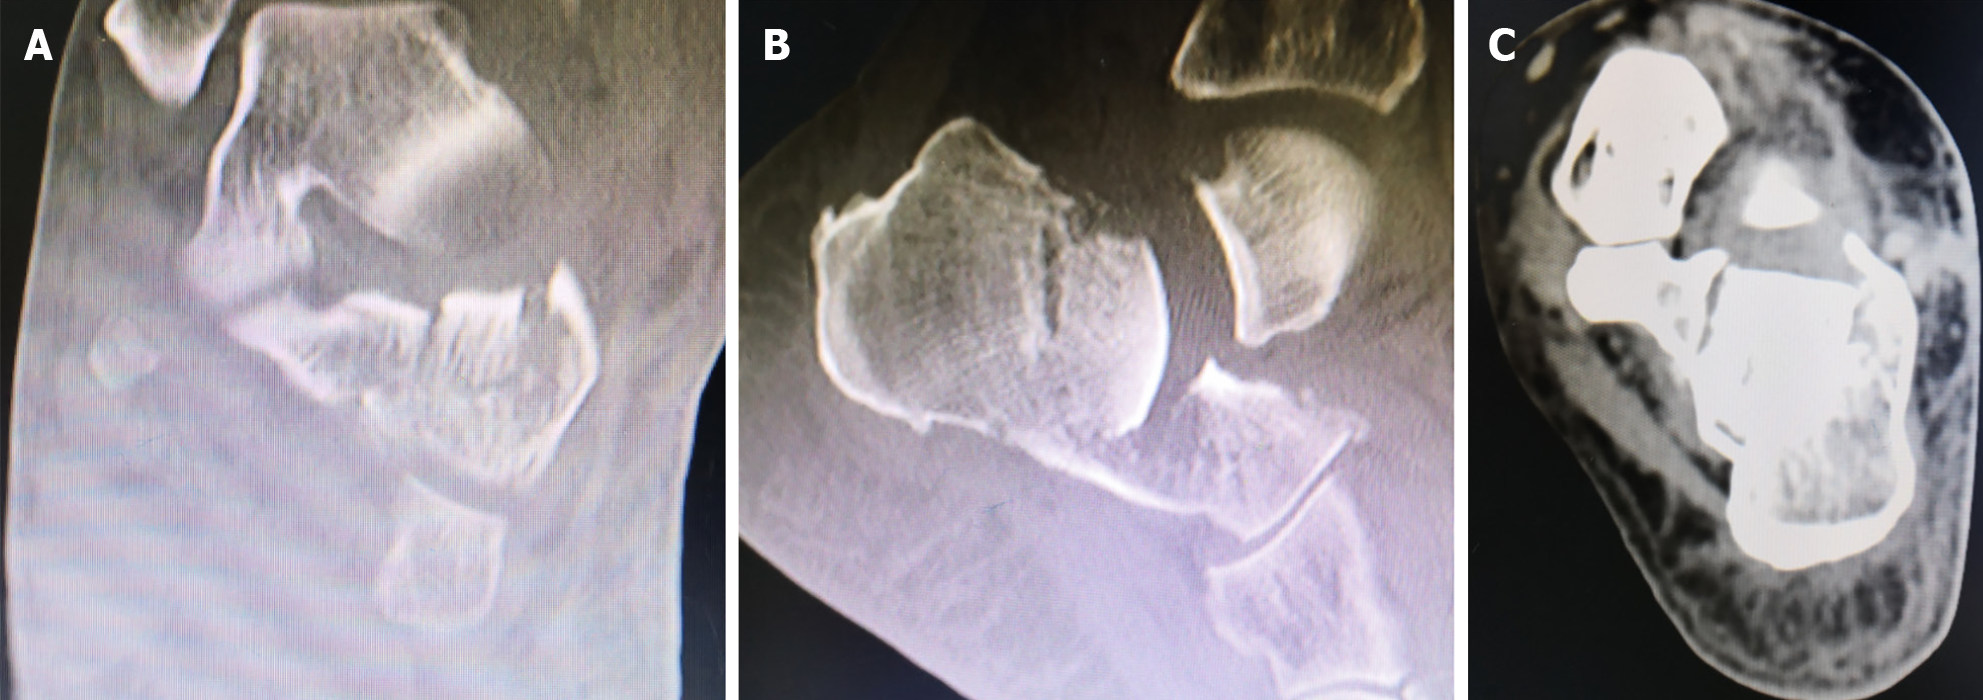

Figure 2 Preoperative computed tomography scan findings.

A: Sanders type IV calcaneal fracture; B: Böhler angle was 0°; C: Mild calcaneal widening.